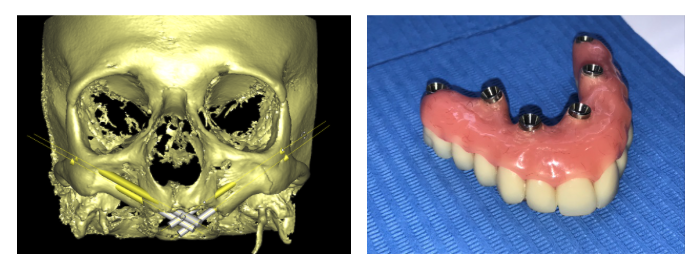

Software de planificación para la colocación de implantes Zigomáticos (Zigoma Quad).

Modelos de planificación 3D para implantes zigomáticos

Modelos 3D de CBCT de esqueleto facial par la planificación de IMPLANTES ZIGOMÁTICOS.

Paciente que precisa rehabilitación y presenta gran atrofia maxilar resuelta con la colocación de 4 implantes zigomáticos.

La planificación fue totalmente digital y los modelos fueron escaneados en 3D. La rehabilitación final ha sido en metal cerámica.

Vista de la planificación 3D, la rx con los zigomas colocados y de la cirugía de colocación de los implantes.

Paciente con atrofia maxilar total por MAXILECTOMÍA izquierda (para tratar un Carcinoma epidermoide)resuelta con la colocación de 4 implantes ZIGOMATICOS. La rehabilitación definitiva ha sido en metal cerámica.

Imagen de la planificación digital del caso y foto final de la paciente con la prótesis metal-cerámica.

Paciente con atrofia total del maxilar, resuelta con Implantes ZIGOMÁTICOS y 1 implante anterior. Planificación informática y Modelos 3D

Imagen de la rx con los implantes colocados, e imagen de la prótesis acrílica.

Paciente con atrofia maxilar total, resuelta con la colocación de 4 implantes zigomáticos. . La prótesis definitiva ha sido realizada en metal-cerámica.

Planificación informática y modelos 3D

Atrofia maxilar total, resuelta con la colocación de 2 implantes zigomáticos y 2 implantes anteriores . Planificación informática y modelos 3D.

Foto de la planificación digital del caso

Atrofia maxilar total, resuelta con la colocación de 2 implantes zigomáticos y 2 implantes anteriores . Planificación informática y modelos 3D.

Foto de la rx tras la colocación de los implantes máxilo-mandibulares

Atrofia maxilar total, resuelta con la colocación de 4 implantes zigomáticos. Planificación informática y modelos 3D

Planificación informática y modelos 3D.